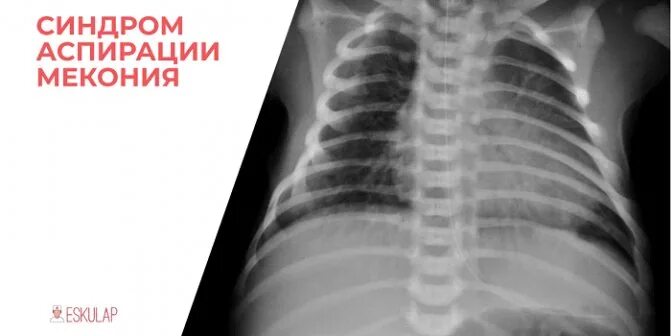

Синдром аспирации